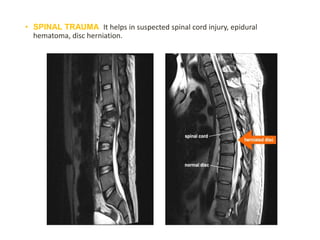

• SPINAL TRAUMA: It helps in suspected spinal cord injury, epidural

hematoma, disc herniation.